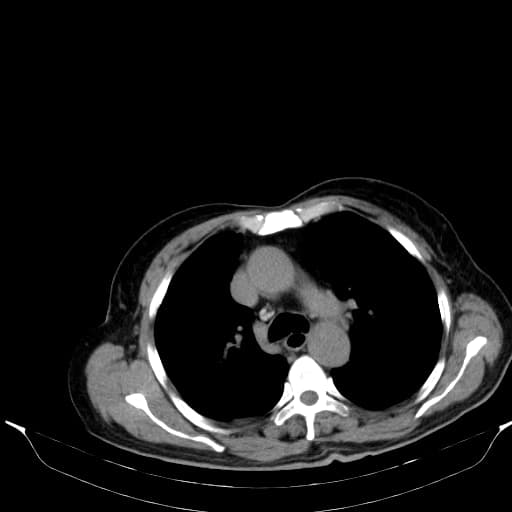

Cắt lớp vi tính (CT)

Sự giãn rộng: Tĩnh mạch chủ dưới bị ảnh hưởng thường bị giãn ra bởi huyết khối.

Kiểu ngấm thuốc: Dấu hiệu đáng tin cậy nhất là sự ngấm thuốc của huyết khối trong thì động mạch (tăng tưới máu). Điều này giúp phân biệt với huyết khối thông thường, vốn không ngấm thuốc (tỷ trọng thấp).

Dấu hiệu "Sợi và vệt" (Thread and Streaks): Các đường ngấm thuốc dạng dải bên trong huyết khối đại diện cho các mạch máu nhỏ.